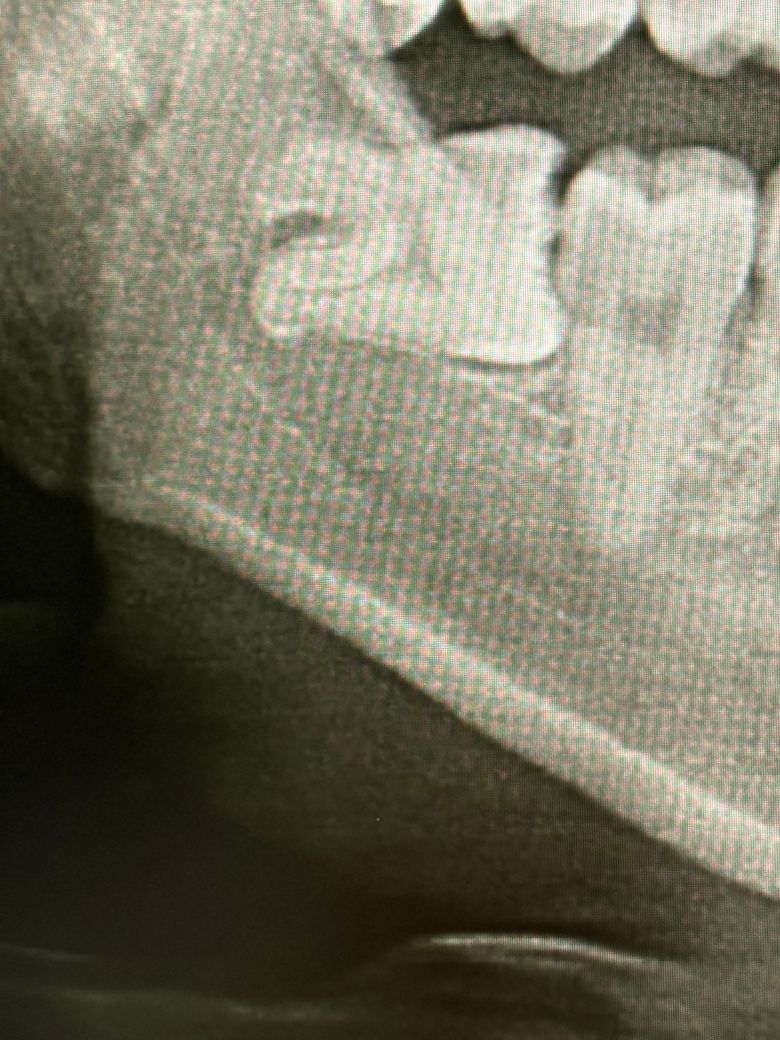

• 2번 째 사진

1. 두번째 엑스레이 기준으로 보면 사랑니 옆 어금니의 옆면 충치는 다소 명확히 보입니다. 또한 사랑니와 어금니 사이 음식물이 끼어 충치가 유발되었을 것으로 강력히 의심됩니다.

1. 저런 경우는 일단 사랑니 발치 후 옆면 충치에 대한 접근이 가능한지 봅니다. 옆구리 쪽으로 접근이 가능한 경우도 있고 힘든 경우 그냥 위에서부터 파고 내려가고 인레이 내지는 크라운을 씌워주게 됩니다.

2. 엑스레이로 보기에는 충치가 다소 크고 깊어서 옆쪽으로 접근은 어려울 수도 있을 것 같습니다.